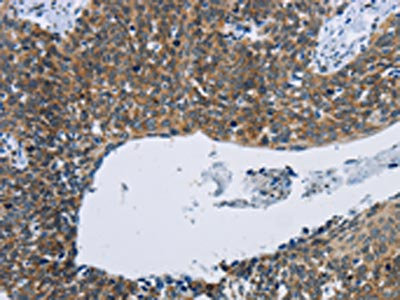

The image on the left is immunohistochemistry of paraffin-embedded Human cervical cancer tissue using CSB-PA244093(KPNB1 Antibody) at dilution 1/40, on the right is treated with synthetic peptide. (Original magnification: ×200)

The image on the left is immunohistochemistry of paraffin-embedded Human thyroid cancer tissue using CSB-PA244093(KPNB1 Antibody) at dilution 1/40, on the right is treated with synthetic peptide. (Original magnification: ×200)